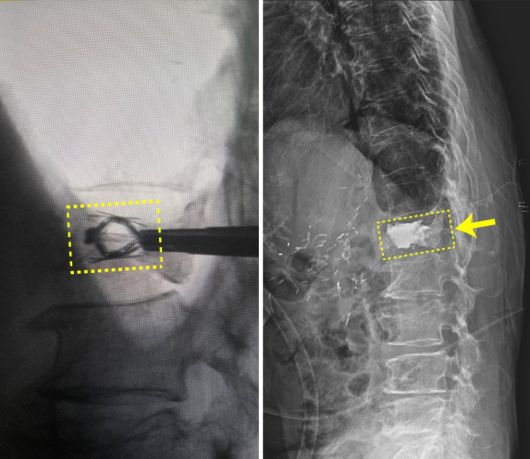

또 허리나 목이 아파 움직임이 어려운 경우에도, 금속 나사, 플레이트, 인공디스크 등을 삽입해 척추를 안정적으로 고정하거나 원활한 움직임을 돕기도 합니다.

[엘앤케이바이오메드 제공] |